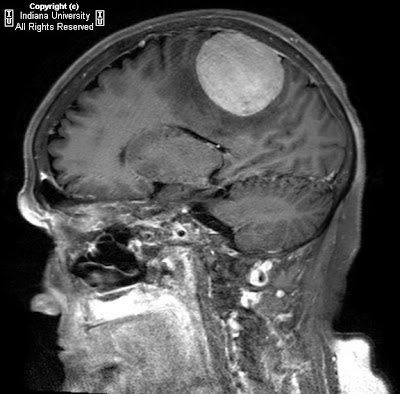

Findings

Imaging characteristics of the tumors in schwannomatosis are the same as those of sporadic schwannomas. Iso/hypointensity on T1 weighted images, hyperintensity (secondary to cystic change, and occasionally hemorrhage) on T2 weighted and STIR images and avid contrast enhancement are typical findings.

Dedicated imaging of the internal auditory canals and the brain should be pursued to help clarify the diagnosis. Follow up imaging is also indicated, especially if the diagnosis is not definitive, as malignant degeneration of an NF2 lesion would manifest as rapid increase in size of a mass.